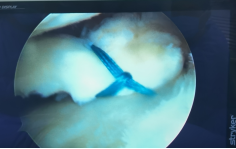

运动医学:肩袖损伤、肩关节脱位、钙化性肌腱炎、膝关节前后交叉韧带损伤、内侧副韧带损伤、内外侧半月板损伤、复发性髌骨脱位、髋关节撞击综合征、肘关节僵硬、慢性踝关节不稳等疾病的微创关节镜手术治疗。